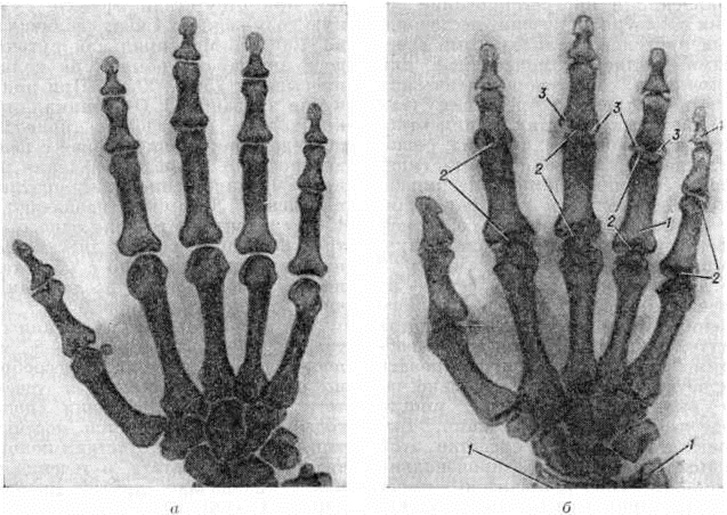

Рентгенодиагностика. В задачи рентгенодиагностики входит, помимо распознавания болезни, также оценка характера, тяжести и распространённости изменений костно-суставного аппарата, определение стадии, а при повторных исследованиях оценка эволюции заболевания. Наиболее распространённой методикой рентгенологическое исследования является стандартная рентгенография суставов. Более детальное изображение структуры кости можно получить, используя безэкранную рентгенографию. Томография (смотри полный свод знаний) при Ревматоидный артрит применяется крайне редко и имеет лишь вспомогательное значение. Поскольку наиболее характерные для Ревматоидный артрит рентгенологическое изменения обнаруживаются у взрослых в кистях и дистальных отделах стоп, а у детей, кроме того, и в шейном отделе позвоночника, эти области исследуют в первую очередь. Динамика рентгенологическое изменений при Ревматоидный артрит отличается медленным темпом, что делает излишним частое повторение исследования.

Продолжительность рентгенонегативного периода при Ревматоидный артрит значительно варьирует и чаще всего составляет от нескольких недель до 1—2 месяцев Ревматоидному артриту свойственны симметричность изменений суставов и склонность этих изменений к прогрессированию. Прогрессируют выявляемые рентгенологические изменения неравномерно, ускоряясь при обострениях болезни и замедляясь, вплоть до полной стабилизации, в периоды ремиссий. У ряда пациентов не отмечается корреляции между клинические, течением болезни и прогрессированием рентгенологическое изменений, в частности рентгенологическое картина может ухудшаться при отсутствии клинические, признаков активности ревматоидного артрита.

При Ревматоидный артрит обнаруживаются разнообразные рентгенологическое симптомы, ни один из которых нельзя считать патогномоничным. Ранние рентгенологическое изменения при Ревматоидный артрит являются неспецифичными, так как свойственны всем артритам (смотри полный свод знаний), и характеризуются утолщением мягких тканей в области поражённых суставов и околосуставным остеопорозом (смотри полный свод знаний). На ранней стадии более чем у половины больных Ревматоидный артрит отмечаются также кистовидные просветления в ближайших к суставам участках костей.

|

|  |

Рис. 6. | ||

В дальнейшем присоединяется сужение суставных щелей, эрозии костей, подвывихи и вывихи (рисунок 7, 8). Часто на фоне описанных изменений на краях суставных поверхностей формируются остеофиты — проявление вторичного артроза. Тяжёлое ревматоидное поражение суставов может приводить к их анкилозированию; в случаях особо неблагоприятного течения возможен остеолиз ближайших к суставам отделов костей (рисунок 9). Как редкие рентгенологическое симптомы встречаются периоститы (смотри полный свод знаний), асептические остеонекрозы (смотри полный свод знаний: Остеохондропатия).

На основании рентгенологическое изменений суставов выделяют стадии Ревматоидный артрит Из многочисленных схем наиболее известна схема Стайнброккера, согласно которой выделяют 4 стадии ревматоидного артрита. К 1-й стадии относят случаи с околосуставным остеопорозом (смотри полный свод знаний), но без сужения суставных щелей и эрозии костей. Если к остеопорозу присоединяется сужение суставных щелей, то это соответствует 2-й стадии. Наличие эрозий костей указывает на 3-ю стадию, а костного анкилоза — на 4-ю стадию. Ларсен (A. Larsen, 1974) предложил более детализированную оценку, выделив 6 стадий, и дал для каждого сустава отдельную схему, отражающую местные особенности проявлений Ревматоидный артрит